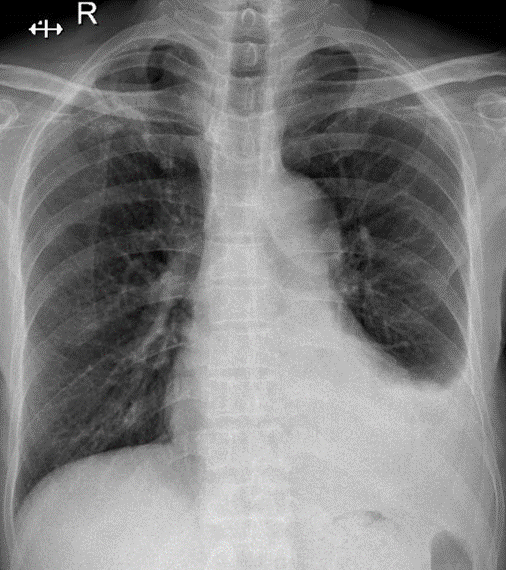

Hãy phân tích tình huống Nam 88 tuổi

1-Xơ thùy trên phổi (P) 2-Tràn dịch màng phổi (T) lượng ít